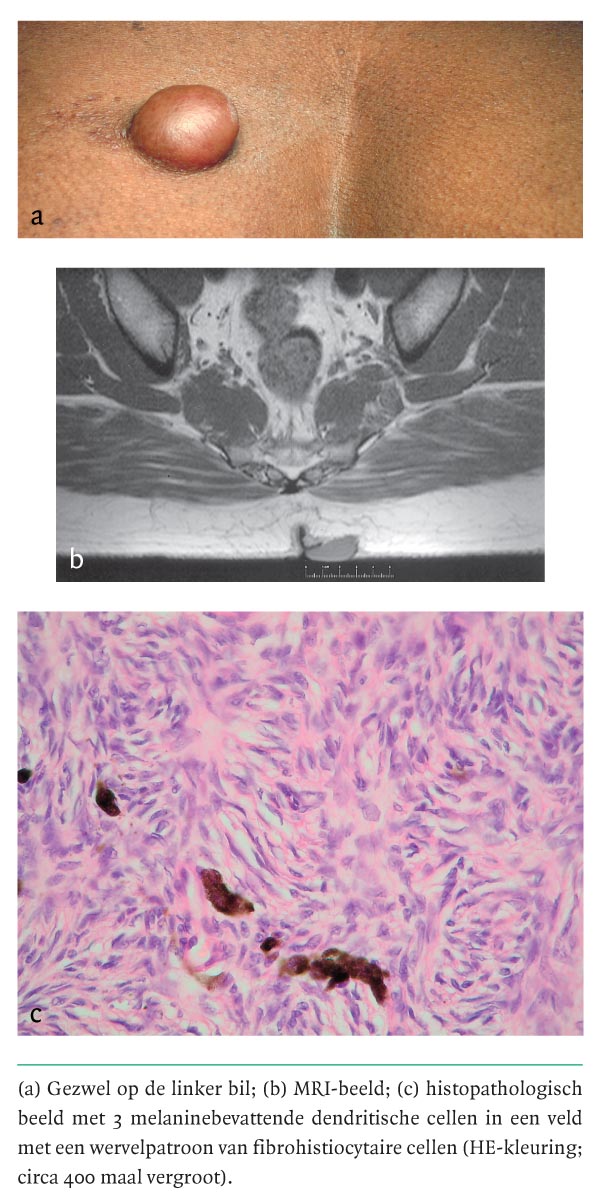

Een 42-jarige man werd via de dermatoloog naar de polikliniek Chirurgie verwezen vanwege een sedert enkele jaren bestaande zwelling op zijn linker bil. De zwelling was langzaam gegroeid en was niet pijnlijk, maar werd wel als hinderlijk en cosmetisch storend ervaren. Bij lichamelijk onderzoek zagen wij een gezonde man met een donkere huidskleur. De zwelling bevond zich ter plaatse van de mediale bovenrand van de linker bil, was vast-elastisch en niet pijnlijk bij palpatie (figuur a). De diameter bedroeg 3 cm. Ten tijde van de verwijzing was een biopt genomen; op basis daarvan was de diagnose ‘Bednar-tumor’…